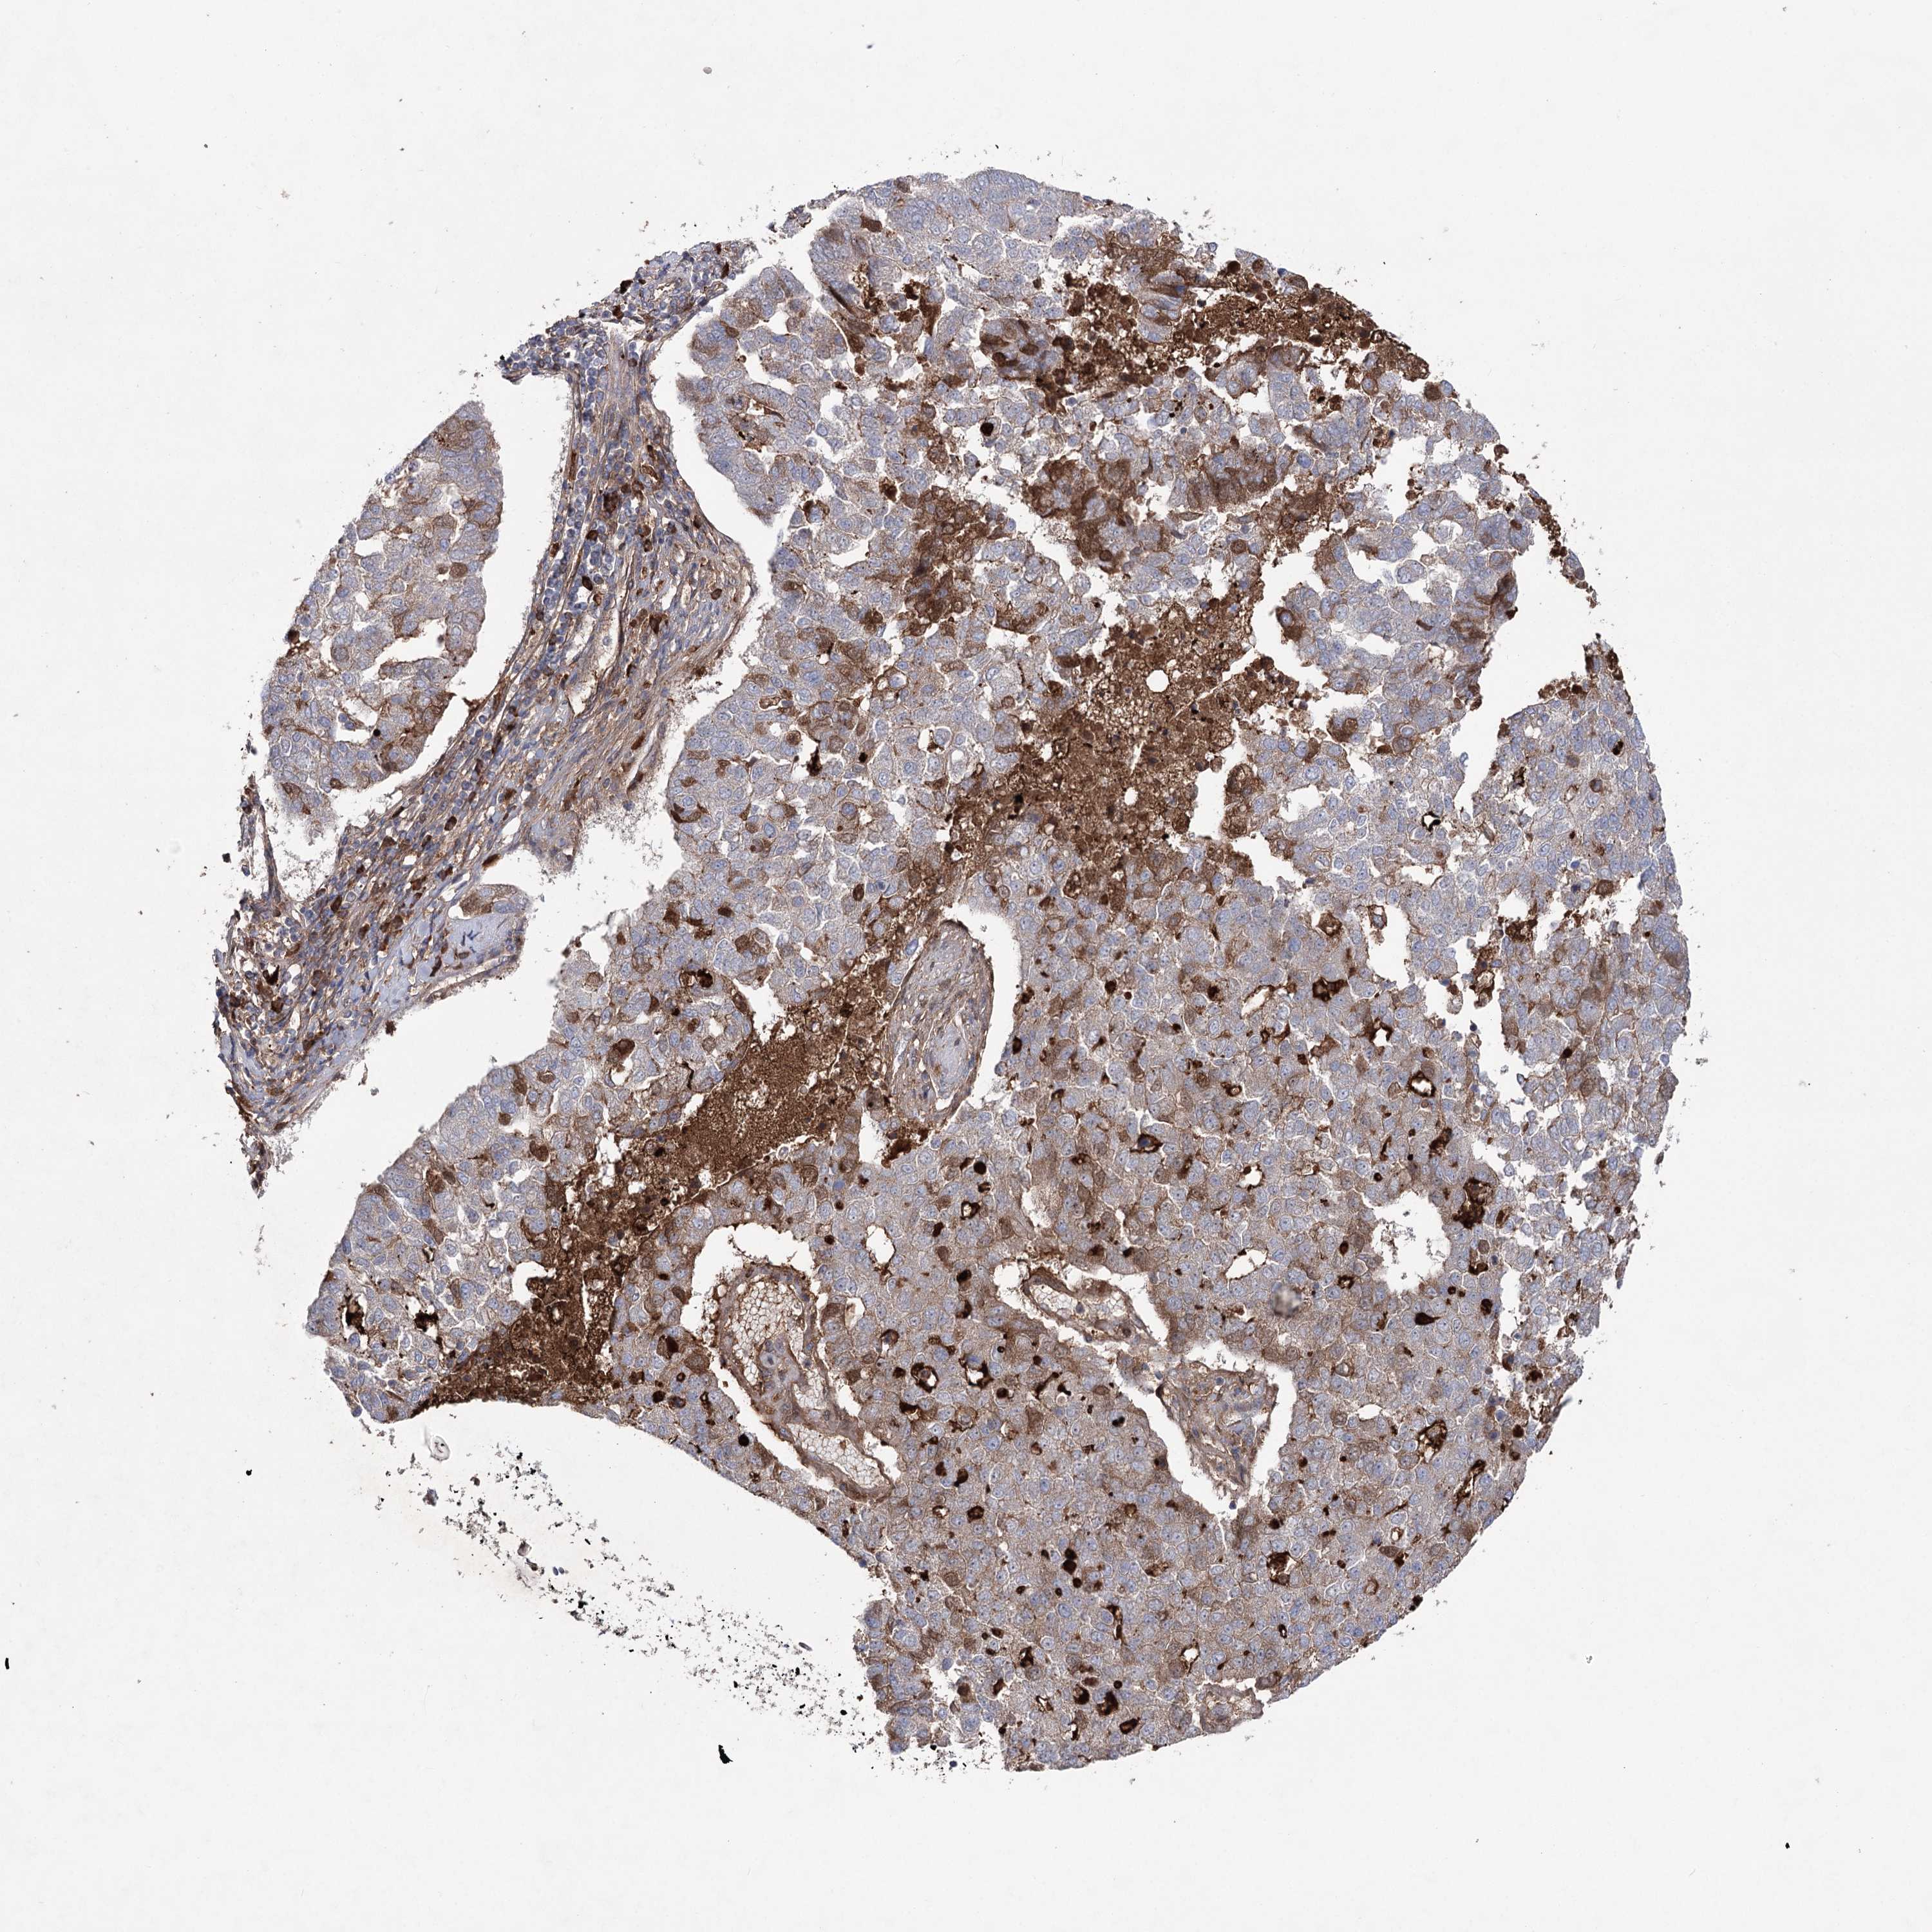

PANCREATIC CANCER - Protein expressioni

A mouse-over function shows sample information and annotation data. Click on an image to view it in a full screen mode. Samples can be filtered based on level of antibody staining by selecting one or several of the following categories: high, medium, low and not detected. The assay and annotation is described here.

Note that samples used for immunohistochemistry by the Human Protein Atlas do not correspond to samples in the TCGA dataset.

Antibody stainingi

Antibody staining in the annotated cell types in the current human tissue is reported as not detected, low, medium, or high, based on conventional immunohistochemistry profiling in selected tissues. This score is based on the combination of the staining intensity and fraction of stained cells.

Each image is clickable and will lead to virtual microscopy that enables deeper exploration of all samples and also displays staining intensity scores, fraction scores and subcellular localization as well as patient and tissue information for each sample.

Antibody HPA038504

Staining

High

Medium

Low

Not detected

Intensity

Strong

Moderate

Weak

Negative

Quantity

>75%

75%-25%

<25%

None

Location

Nuclear

Cytoplasmic/membranous

Cytoplasmic/membranous,nuclear

Adenocarcinoma, NOS